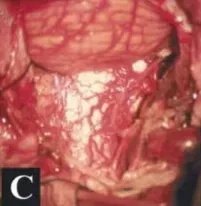

▼术中及肿瘤切除后的硬膜内部位